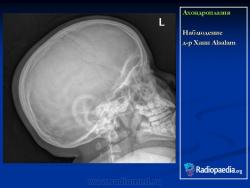

Наблюдение д-ра Франк Гайар

Ахондроплазия

http://radiopaedia.org/images/392220

http://radiopaedia.org/cases/achondroplasia